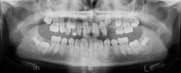

X-Rays and Cephalometric Tracings

pan xray ceph tracing measurements patienthist

Panoramic Intraoral Lateral Ceph Ceph Tracing Cephalometric Summary Patient History